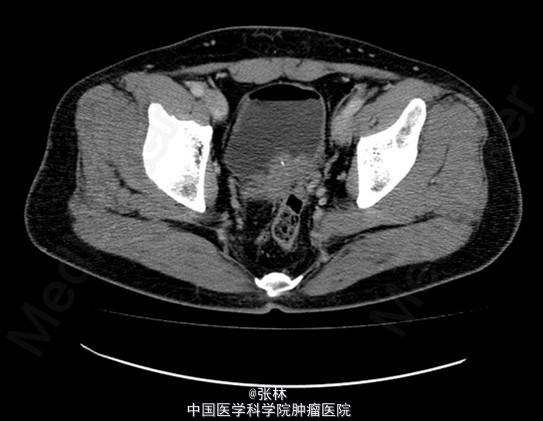

CT:膀胱充盈尚可,内见积气、气液平面;膀胱后壁明显不规则增厚,形成肿物,边界不清,范围约4.8×2.8cm,膀胱壁外缘毛糙,局部与直肠前壁分界不清。考虑:膀胱后壁肿物,与直肠关系密切,考虑为恶性。 MR:膀胱左后壁肿物,与精囊腺及后方直肠分界不清,膀胱充盈状态不同,形态较前改变,现范围约3.6×4.2cm,边界不清楚,T1WI呈低信号,T2/FS呈高信号,DWI扩散受限,增强扫描呈明显不均匀强化,考虑为恶性。